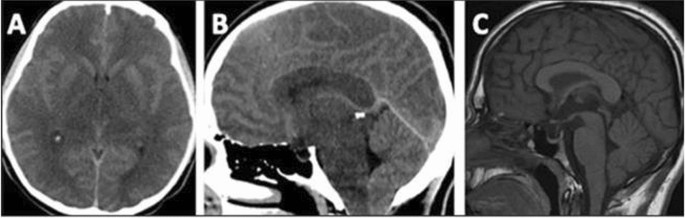

Patient 1: A 21-year-old male patient presented with nausea, vomiting, and reduced oral intake for 3 days. He looked lethargic, although fully conscious, with a GCS of 15/15. Due to poor dietary compliance, plasma leucine levels were chronically elevated (1300–1600 µmol/L) for 1 year prior to this episode. He was admitted as a case of metabolic decompensation and received conservative treatment with IV dextrose in saline infusion, BCAA-free formula and dietary natural protein restriction. The next day of admission, he had a headache and transient abnormal hand movements. A CT scan of the brain showed diffuse cerebral edema causing cerebellar tonsillar herniation (Fig. 1: A and B). He remained fully conscious with no focal neurological signs. Plasma leucine was 1300, isoleucine 237 and valine 271 µmol/L. He was shifted to the ICU and received continuous renal replacement therapy (CRRT) for 48 h until leucine levels were reduced to 400 µmol/L. Conservative management continued with hypertonic saline infusion, high-calorie intake, BCAA-free formula and valine and isoleucine supplements. He remained clinically stable and asymptomatic; however, a repeat CT scan after 5 days showed persistent diffuse cerebral edema and cerebellar tonsillar herniation.

Brain imaging of patient 1 Head-CT at the initial presentation shows diffuse brain edema (A and B), causing cerebellar tonsillar herniation (B). Sagittal T1 from the following MRI brain shows improved edema and resolution of tonsillar herniation (C)

Following discharge from the hospital, the patient developed bilateral visual impairment. His leucine levels were satisfactory (200 µmol/L). Ophthalmological examination revealed severe bilateral papilledema with a visual acuity of 20/200 in the right eye and 20/300 in the left eye. A repeat CT scan showed improvement in cerebral edema with persistent but improved cerebellar tonsillar herniation. He was prescribed acetazolamide for papilledema. Plasma leucine levels were 200–600 µmol/L in the following few months. CT brain scan after 12 weeks of the initial presentation showed further improvement of cerebral edema and resolution of cerebellar tonsillar herniation. However, his vision remained poor, which justified magnetic resonance imaging (MRI; Fig. 1C) demonstrating persistent brain edema in a distribution compatible with MSUD extending to the optic tracts. The optic nerves were mildly atrophic, with a mildly abnormal signal in the optic chiasma. His dietary compliance, which initially improved for a few months after discharge from the hospital, gradually worsened.